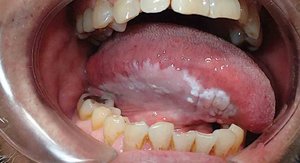

Conditions of the Mouth

Cancer: Often linked to tobacco and alcohol; leukoplakia and squamous cell carcinoma are common forms.

Thrush: Oral candidiasis (yeast infection), common in children and immunocompromised individuals.